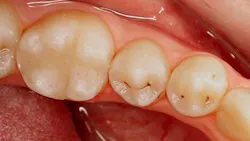

One of the most common decisions for restorative dentists comes during initial and recall examinations. This decision is a “yea” or “nay” on whether the clinician will diagnose the presence of caries in the pits and fissures of the patient’s dentition. Clinicians use visual cues in conjunction with a dental instrument, such as a dental explorer, to do so. Figure 1 shows a clinical case in which many of us would monitor tooth no. 20, and just as many of us would restore no. 20.